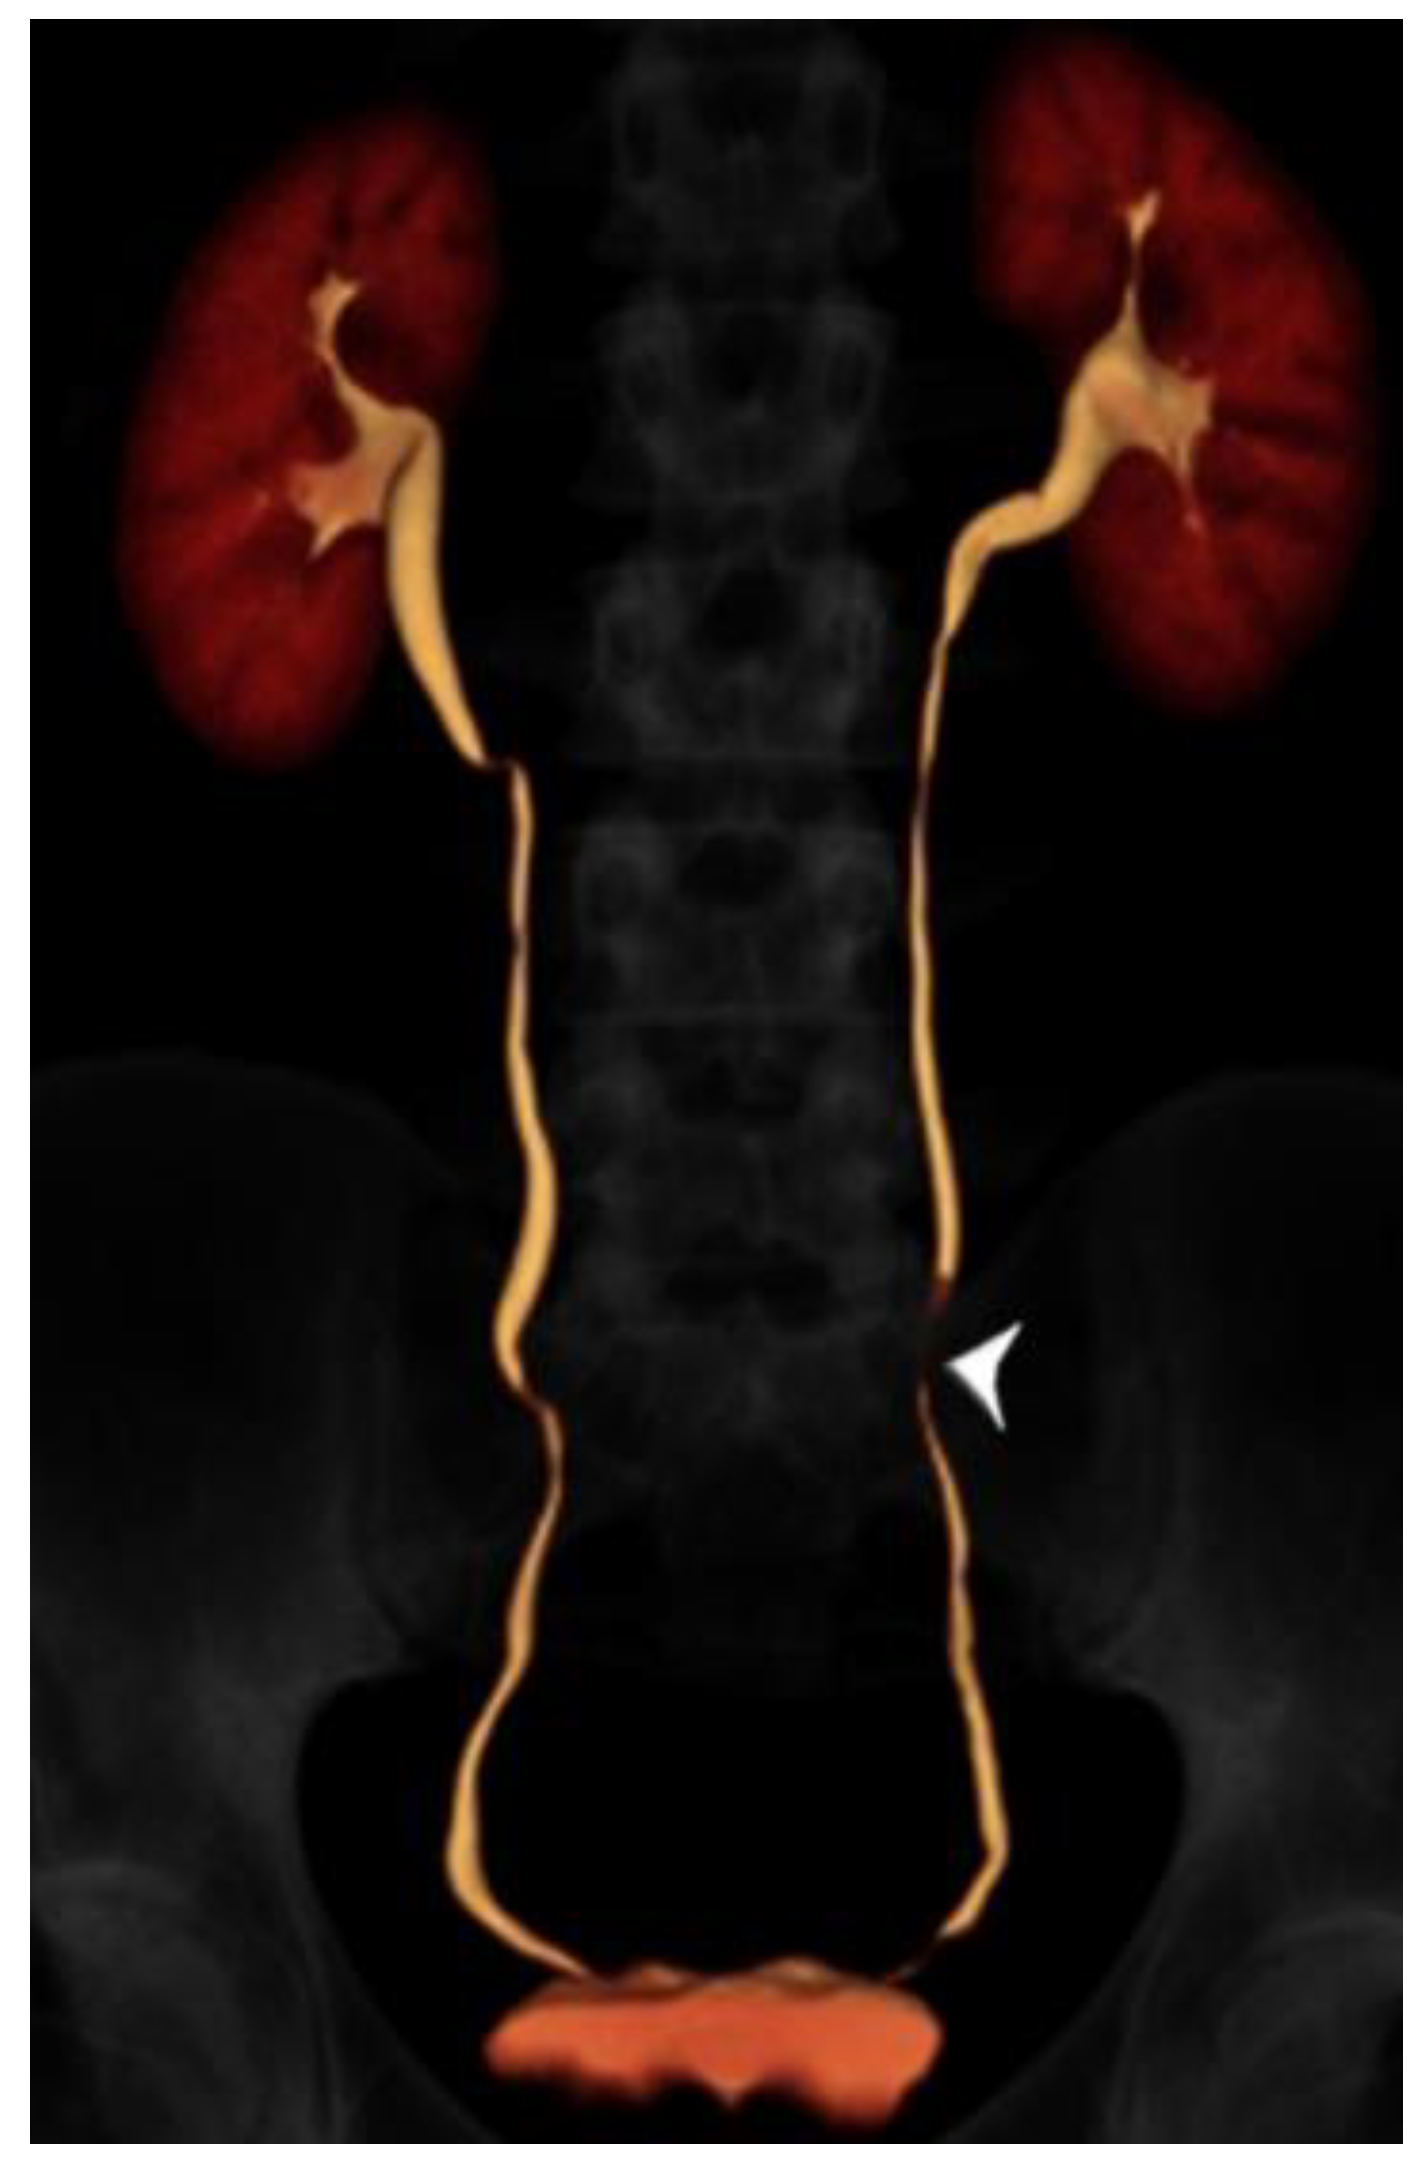

2.2. CT Urography Technique

- Cheng, K.; Cassidy, F.; Aganovic, L.; Taddonio, M.; Vahdat, N. CT urography: How to optimize the technique. Abdom. Radiol. 2019, 44, 3786–3799. [Google Scholar] [CrossRef]